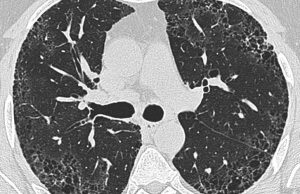

Etiket: İPF hastalığı

Astım ya da KOAH ile karıştırılan ve henüz kesin bir tedavisi...

Dünya İPF Haftası nedeniyle bir açıklama yapan TÜSAD, belirtileri astım ya da KOAH ile...